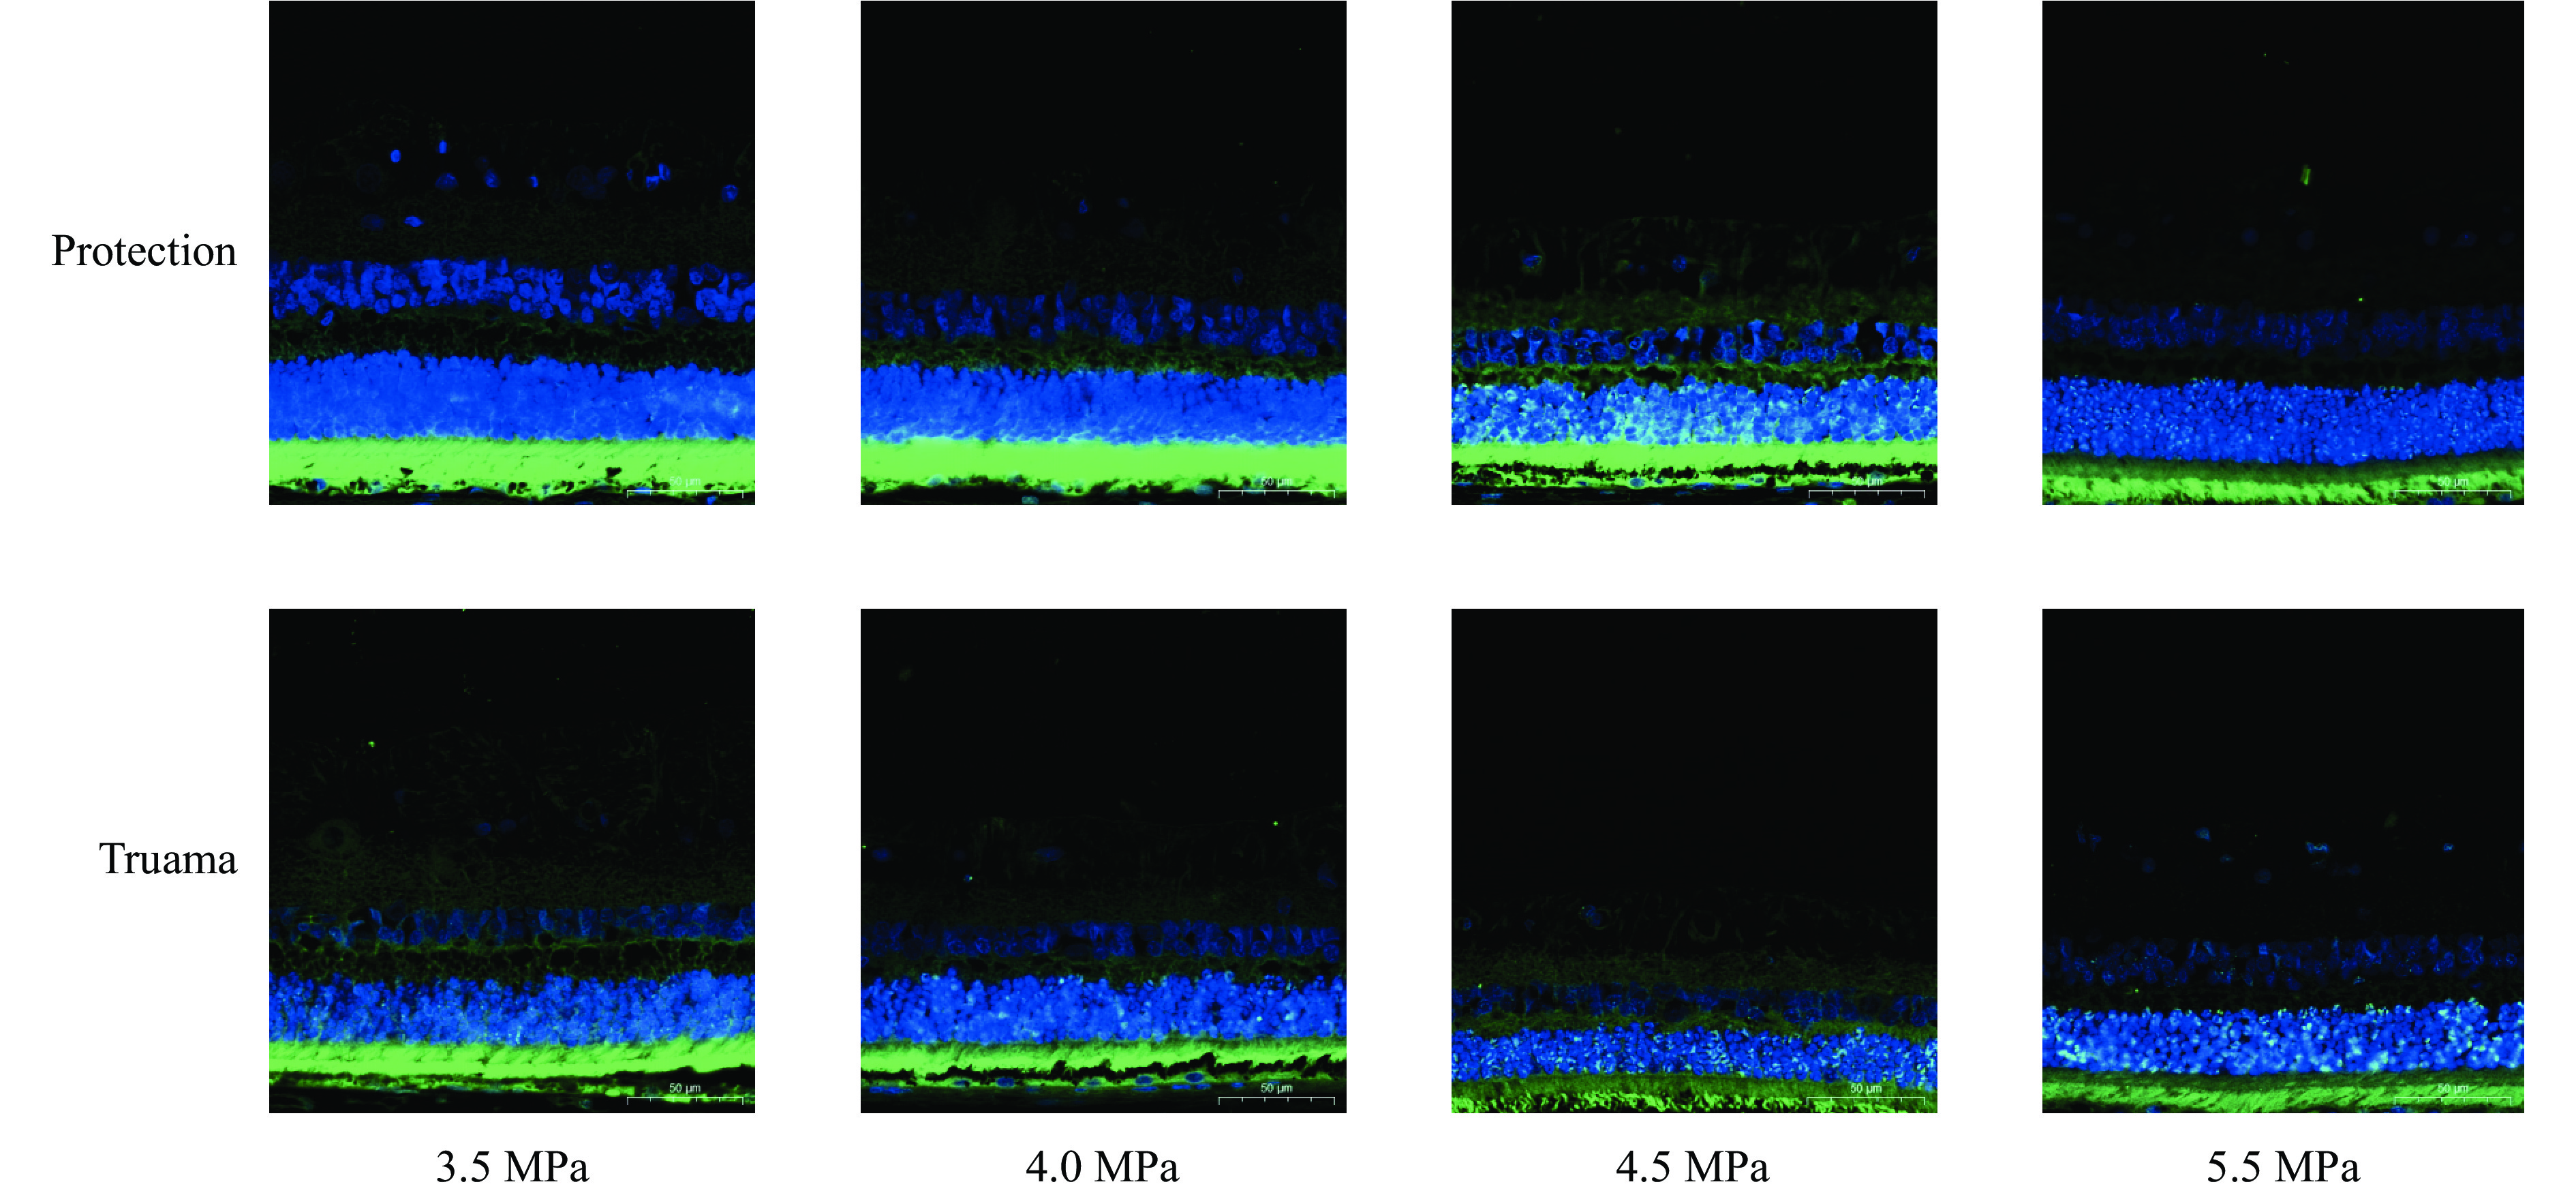

We firstly verified the protective performance of eye equipment (goggles) based on a head dynamic test system and shock tube and field live blast test environments. The results show that goggles have better protective performance and suggest that duty personnel should be equipped with goggles that have combined functions of anti-ultraviolet, anti-glare, anti-smoke and anti-fragmentation in to improve eye protection capabilities. After that, we investigated the tissue damage and functional impairment changes after explosive eye blast injury, and the protective effect and mechanism of the goggles for animal experimental version. This may provide a theoretical basis for prevention and treatment, and also have important implications for the design and improvement of protective goggles. Beagles and C57 mice were used for related animal experiments, and the changes in retinal layer thickness and cell apoptosis were observed after blast injury by HE, Tunel, Nissl staining, visual electrophysiology detection and other methods. It was found that with the increase of blast intensity and the extension of time after explosion, both the degree of retinal injury and cell apoptosis increased, among which the ganglion cell layer and photoreceptor inner and outer segments suffered the most severe damage. Further research on molecular changes indicates that the expression levels of autophagy-related regulatory proteins SQSTM1/p62 (P <0.0001 ) and LC3-Ⅱ (P = 0.8437 ), as well as LC3-Ⅰ (P = 0.003), are significantly increased, suggesting that retinal damage is, to some extent, induced by autophagic mechanisms. The protective goggles could effectively reduce the damage of blast wave to retina, protect the structural integrity of retinal nerve fiber layer, inner and outer nuclear layer, ganglion cell layer and photoreceptor inner and outer segments. At the same time, compared with that of other groups, the difference in retinal layer thickness and cell apoptosis was most significant in the 3.5 MPa group, suggesting that the glasses played the maximum protective effect at this intensity, which may be related to the reduction in the retinal autophagy.

We firstly verified the protective performance of eye equipment (goggles) based on a head dynamic test system and shock tube and field live blast test environments. The results show that goggles have better protective performance and suggest that duty personnel should be equipped with goggles that have combined functions of anti-ultraviolet, anti-glare, anti-smoke and anti-fragmentation in to improve eye protection capabilities. After that, we investigated the tissue damage and functional impairment changes after explosive eye blast injury, and the protective effect and mechanism of the goggles for animal experimental version. This may provide a theoretical basis for prevention and treatment, and also have important implications for the design and improvement of protective goggles. Beagles and C57 mice were used for related animal experiments, and the changes in retinal layer thickness and cell apoptosis were observed after blast injury by HE, Tunel, Nissl staining, visual electrophysiology detection and other methods. It was found that with the increase of blast intensity and the extension of time after explosion, both the degree of retinal injury and cell apoptosis increased, among which the ganglion cell layer and photoreceptor inner and outer segments suffered the most severe damage. Further research on molecular changes indicates that the expression levels of autophagy-related regulatory proteins SQSTM1/p62 (P <